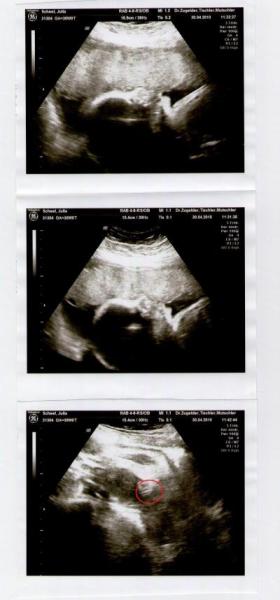

Also wir bekommen eine kleine Prinzessin...

Sie ist zwar relativ klein aber sehr aktiv. Liegt momentan wieder in BEL

aber der FA meinte sie dreht sich bestimmt nochmal.

CTG war auch super, hatter während des CTGs schluckauf bekommen. Wehentätigkeit gab es nicht, aber sehr viele Kindsbewegungen. Da hat sogar der FA gestaunt.

Hier noch die Werte:

Gewicht 1302 g +- 190 g

BPD 7,32 cm

OFD 9,81 cm

KU (Merz) 27,10 cm

AU 23,59 cm

TAD 7,47 cm

FL 5,74 cm

Habe zwar selbst keine Ahnung was das alles heist, aber ihr wisst es bestimmt...

Der FA meinte er wisse nicht, warum die kleine so zierlich ist, da die durchblutung sehr gut ist und alles andere auch. Wird wahrscheinlich so klein sein wie mein Mann damals.

Hier noch ein Bild von unserer Kleinen!!!